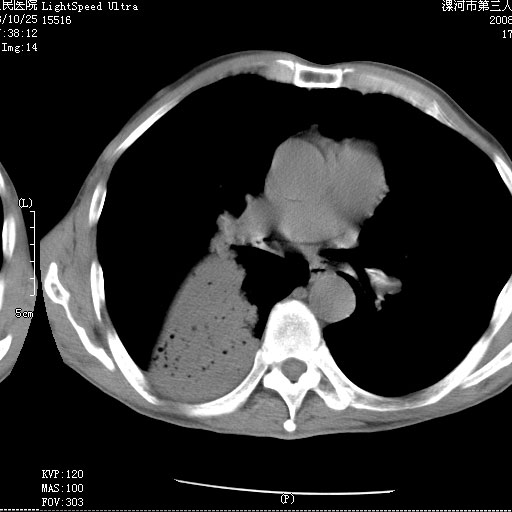

m 老年 发烧、呼吸困难,慢支、肺气肿多年;记的那次是下午大概17:38做的,晚上窒息死亡。

上面的层面就慢性支气管炎肺气肿、肺大泡,别的没有什么、也就不传了。

当时我怀疑:1、阻塞性肺不张早期 2、肺脓肿早期,望老师们发表意见

应该是脓胸的表现,右下肺气管阻塞考虑为痰栓.

你怀疑的有道理,慢支、肺气肿、肺打泡是有了,右下肺的病变有待商议;

首先考虑右下肺炎症并不张,不除外早期肺泡癌改变

病灶边缘清---多个含气小腔---近端未见通畅气管影-----支持-----慢性肺脓肿继发阻塞性肺不张

阻塞性肺不张原因-----脓液未排出

1、右侧脓胸;2、copd;

3、细支气管肺泡癌可以排除,病变以斜裂为界,呈大片状高密度影,内可见多发小气泡,表明有产气杆菌感染所致,内无明显的支气管“枯树枝征”表现,再结合其临床改变(细支气管肺泡癌临表表现重、影像表现轻)所以不符合细支气管肺泡癌(炎症型)的改变。